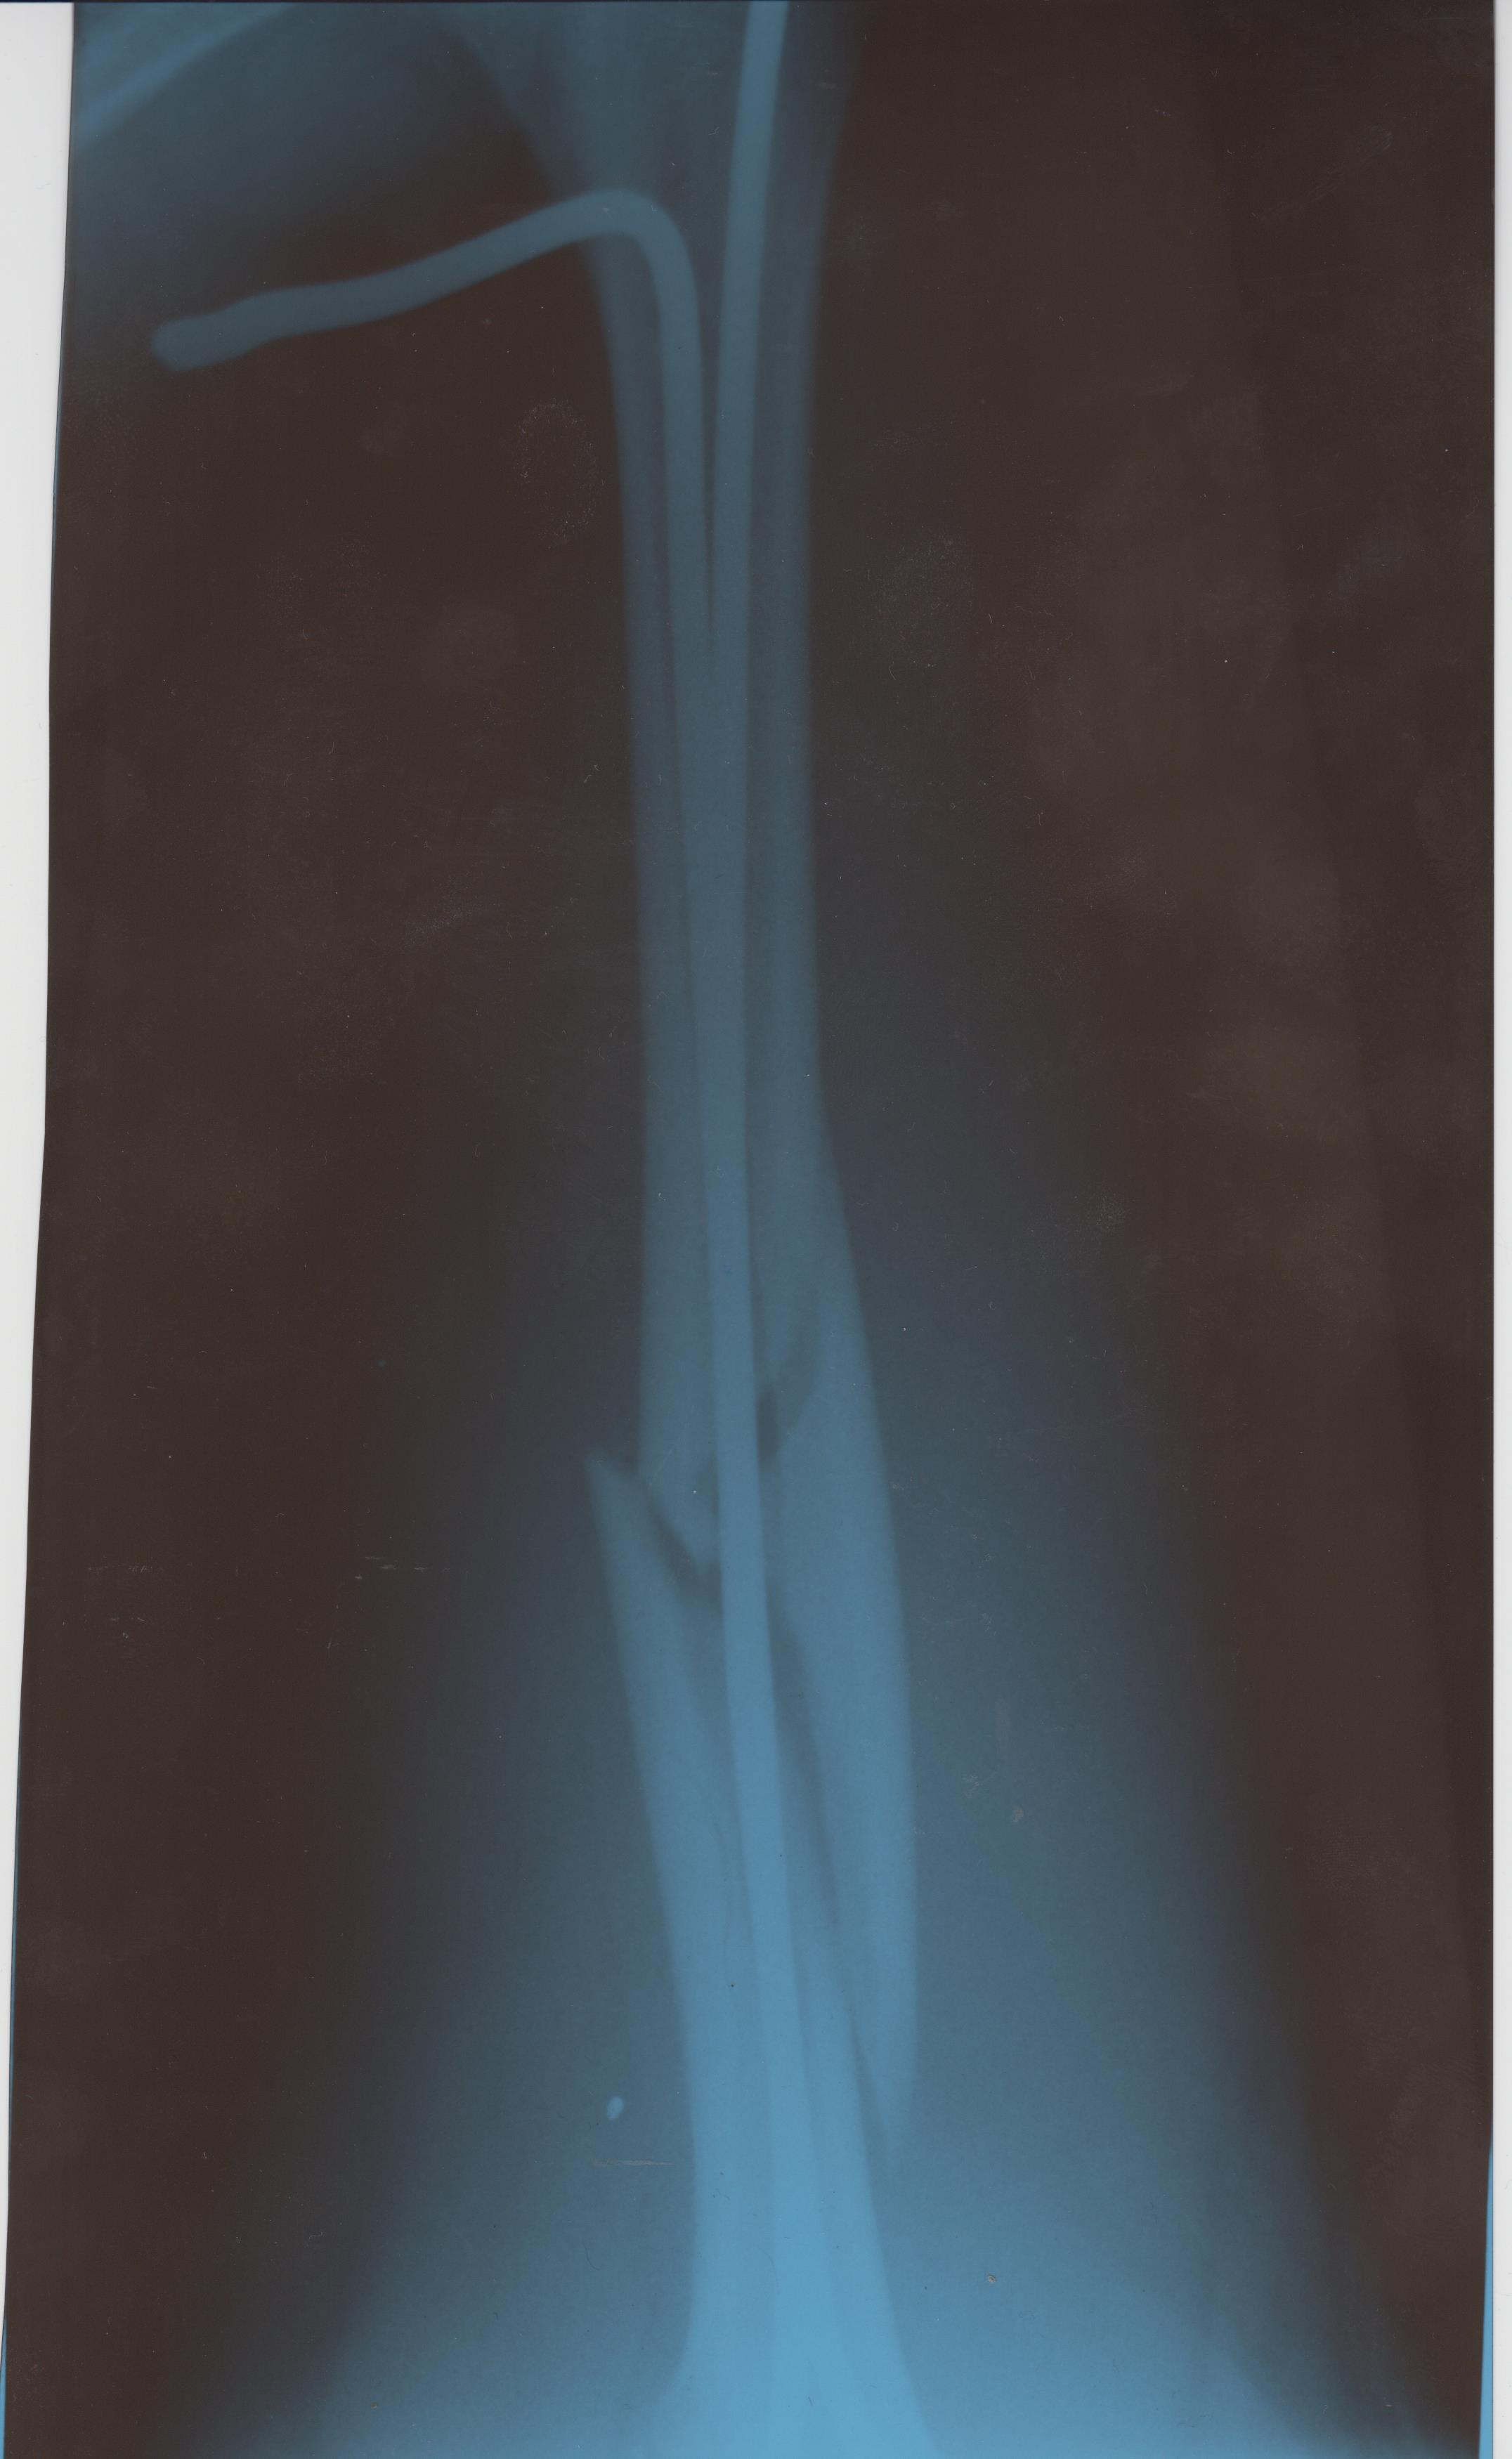

Соревнования по дзюдо. Татами. Схватка. Подсечка. Скорая. Детская травмотология. Перелом бедра со смещением. Вытяжка. Операция. Костыли.

З.Ы. На ноге вдоль кости вставили два штыря. Через полгода будут изымать. Я в технологиях не силен, сказать что это не могу.

Добавил сканы снимков. Самый первый не удалось снять, он очень большой, сканер никак взять не мог.